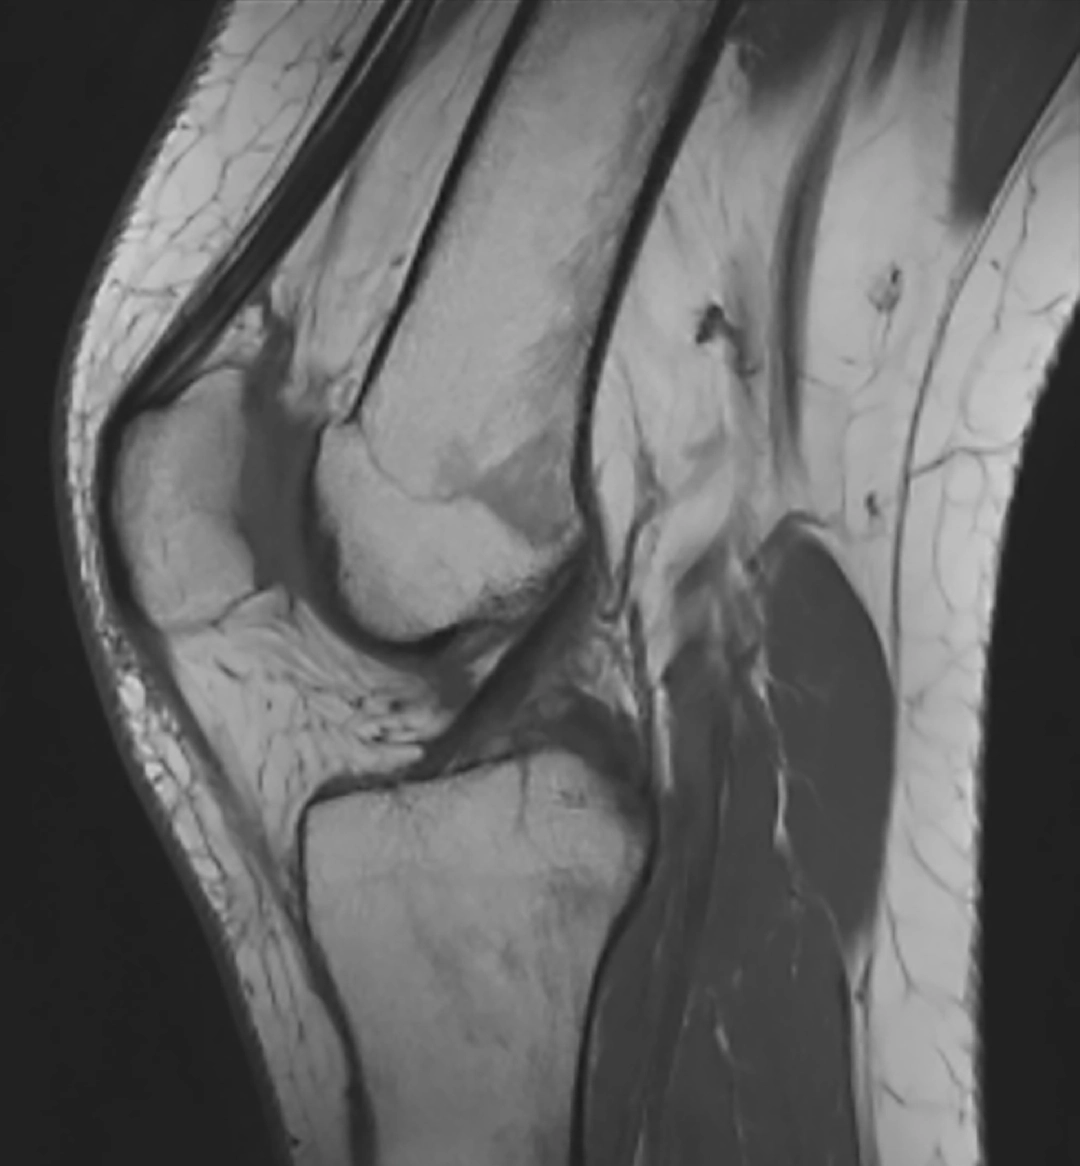

La RM 3T permite obtener imágenes de altísima resolución, con un nivel de detalle superior al de los equipos convencionales. Gracias a ello, se facilita la correcta valoración de estructuras complejas como:

Cartílago

Meniscos

Ligamentos

Tejidos blandos

Esta capacidad de detalle resulta fundamental para detectar lesiones con mayor exactitud y reducir el margen de error diagnóstico.

Estudio de rodilla mediante RM 3 Teslas de VOT, con alta definición anatómica y excelente contraste tisular para una valoración precisa de estructuras osteoarticulares y partes blandas.